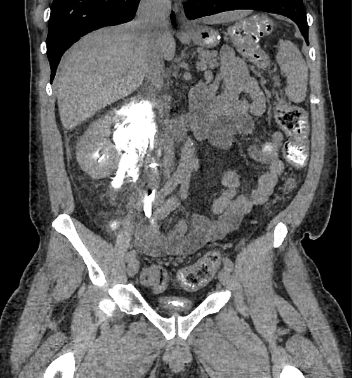

Imagen 6. Imagen de reconstrucción coronal de tomografía abdominal sin contraste (pielotomografia) donde se identifican imágenes hiperdensas en ambos riñones a nivel de pirámides renales, así mismo se observa la presencia de colección perirrenal derecha.

Ambos riñones se observan con presencia de imágenes hiperdensas en sitio anatómico de pirámides renales (valores de atenuación de hasta 1082UH) con presencia de colección perirrenal con densidad liquido (12UH) rodeando riñón derecho. Se observa estriación de la grasa en plano retroperitoneal derecho, extendiéndose hasta fosa iliaca derecha.

Imagen 7. Reconstrucción 3D de una tomografía abdominal sin contraste donde se identifica presencia de litos con densidad cálcica intrarrenales.

Presencia de Lito de grandes dimensiones en tercio medio de uréter derecho, con hidronefrosis secundaria. Atenuación (1500UH).

Imagen 12 y 13. Magnificaciones de una tomografía abdominal sin contraste Demostrando la presencia de imágenes hiperdensas, dispuestas de forma difusa en pirámides renales,con presencia de colección perirrenal derecha, aumentado de tamaño.